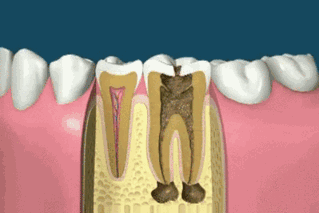

Si la carie est particulièrement grave et a endommagé le nerf de la dent, un traitement de canal peut être effectué en premier lieu pour éliminer la carie et l'inflammation. Si la partie restante de la dent est trop petite, un inlay peut être réalisé, ou une couronne peut être fabriquée pour la protéger et essayer de ne pas extraire la dent.

Si la pulpe n'est pas blessée et ne provoque pas de pulpite, il est généralement possible d'obturer directement la dent ! Le prix est également relativement bon marché, il y a généralement plusieurs types de matériaux à choisir, plusieurs centaines de dollars ! Si la pulpe de la dent est suffisamment profonde pour provoquer une pulpite, vous devrez subir un traitement de canal ! Qu'est-ce qu'un traitement de canal ? Cela signifie simplement que le nerf de la dent est tué et qu'une fois le traitement de canal effectué, la dent ne fera plus jamais mal !